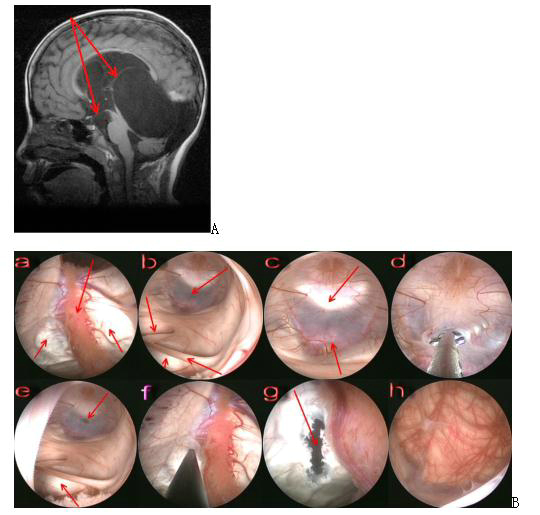

图7. A手术前磁共振图像,显示四叠体池蛛网膜囊肿向上突入侧脑室,箭头指示为第三脑室底部造瘘以及囊肿-侧脑室造瘘方向;B 手术中截图,内镜下可见四叠体池蛛网膜囊肿手术步骤。A:内镜进入侧脑室,下方双侧箭头指示突入侧脑室的囊肿顶部,上方箭头指示脉络丛;b:内镜进入第三脑室,右上方箭头指示第三脑室底,右下方箭头指示被牵拉伸长的中间块,左侧上方箭头指示被挤压闭合的导水管上口,左下方箭头指示突入第三脑室的囊肿壁;c:第三脑室底,上方箭头指示鞍背,下方箭头指示基底动脉;d:第三脑室底造瘘;e:第三脑室底造瘘后,上方箭头指示造瘘口,下方箭头指示突入第三脑室的囊肿壁;f:在突入侧脑室的囊肿顶部造瘘;g:箭头指示造瘘口部位;h:内镜经造瘘口进入囊肿内,可见下方小脑上表面。